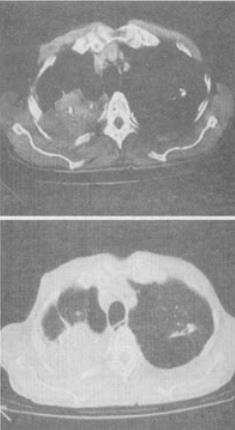

患者男,67岁,胸痛、咯血、体重下降,结合CT检查,最可能的诊断是()。

A、肺结核

B、肺上沟瘤

C、错构瘤

D、胸膜间皮瘤

E、神经鞘瘤

B